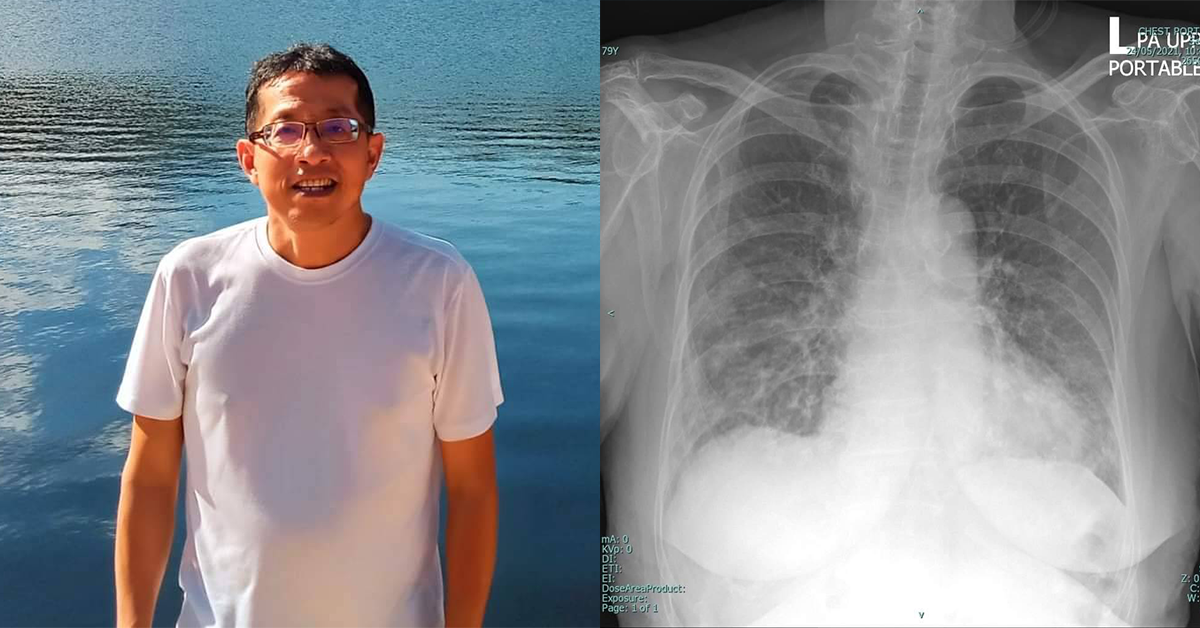

จากกรณีการเสียชีวิตของผู้ป่วยอาการปอดติดเชื้อแบคทีเรียหลังจากรักษาโควิด-19 หายที่โรงพยาบาลศรีสะเกษเมื่อวันที่ 22 พ.ค. ที่ผ่านมา ล่าสุดเมื่อนวันที่ 24 พ.ค. พ.นิธิพัฒน์ เจียรกุล หัวหน้าสาขาวิชาโรคระบบการหายใจและวัณโรค ภาควิชาอายุรศาสตร์ คณะแพทยศาสตร์ศิริราชพยาบาล มหาวิทยาลัยมหิดล ได้เผยข้อความถึงประเด็นการเสียชีวิตของผู้ป่วยรายดังกล่าวโดยระบุว่า

อ่านข่าวแล้วไม่สบายใจ ผู้เสียชีวิตจากโควิด-19 ในต่างจังหวัดคงมีอีกหลายรายเช่นรายนี้ ที่ผู้บริหารซึ่งรับผิดชอบให้ข่าวว่าเสียชีวิตจากเหตุอื่น ที่จริงหมอพวกนี้ถือว่าจงใจปกปิดข้อมูลทำให้ภาพรวมการเสียชีวิตจากโควิดต่ำกว่าความเป็นจริง ส่งผลให้ภาคความมั่นคงและภาคประชาชนไม่เห็นความสำคัญของปัญหาที่แท้จริง และไม่กวดขันเข้มงวดเพื่อช่วยลดการสูญเสียของการระบาดในวงกว้าง ปัจจุบันแพทย์รุ่นใหม่โดยเฉพาะอายุรแพทย์ จะถูกสอนและเน้นย้ำความสำคัญการลงรหัสโรค การสรุปรายงานผู้ป่วย และการลงสาเหตุการเสียชีวิต ดังตัวอย่างที่ผู้ป่วยเป็นปอดอักเสบโควิดใช้เครื่องช่วยหายใจเป็นเวลานานจนตรวจไม่พบเชื้อโควิดแล้ว

ต่อมาเกิดปอดติดเชื้อแบคทีเรียแทรกซ้อนและเสียชีวิต การสรุปสาเหตุการตายต้องเป็นโรคโควิด-19 โดยมีปอดอักเสบจากเชื้อแบคทีเรียเป็นภาวะแทรกซ้อน เข้าใจว่าพวกนี้ชอบซุกขยะใต้พรม ตกแต่งตัวเลขในความรับผิดชอบให้ดูสวยงามเข้าไว้ คิดแล้วเศร้าใจแทนประชาชนไทย แต่ยังไงก็ไม่ขอเปลี่ยนประเทศ เพราะมันเป็นหนึ่งในสิ่งสำคัญของรักของหวงของผมไปแล้ว